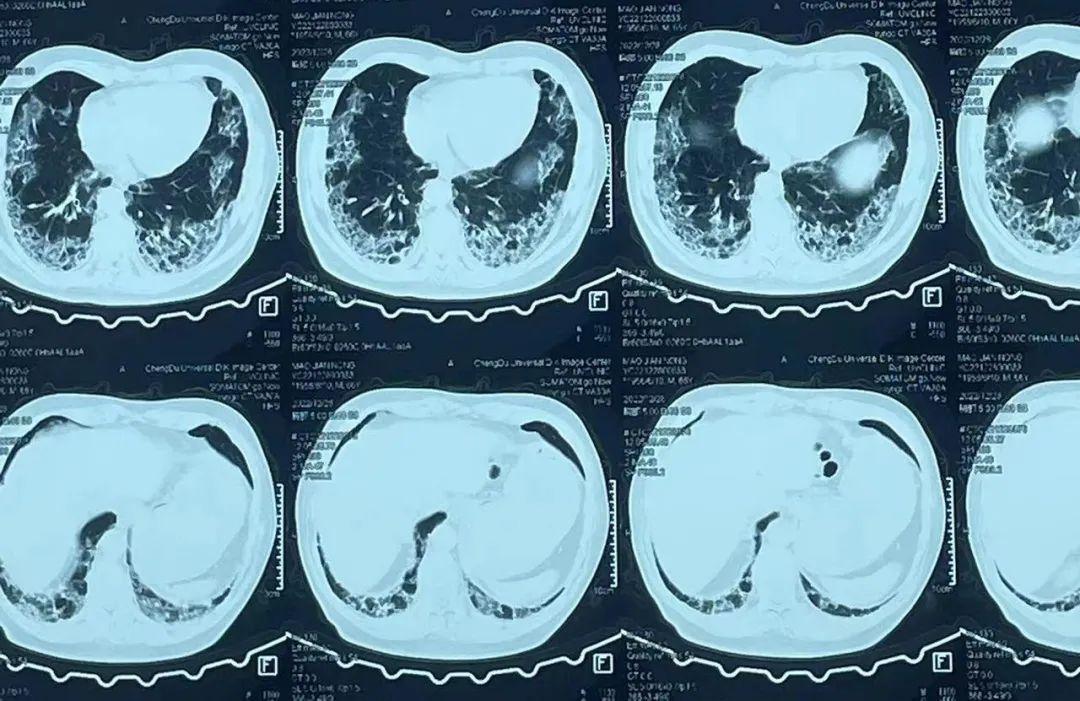

白肺,一般是指在X光或者CT检查下,肺部显影呈一片白色。主要由肺部细菌感染或人体炎症反应所致。

但并不是肺部只要出现了炎症就都叫白肺,一般来讲肺部炎症较重、渗出液较多,白色的影像区域面积达到70%一80%时,才把它称为白肺。